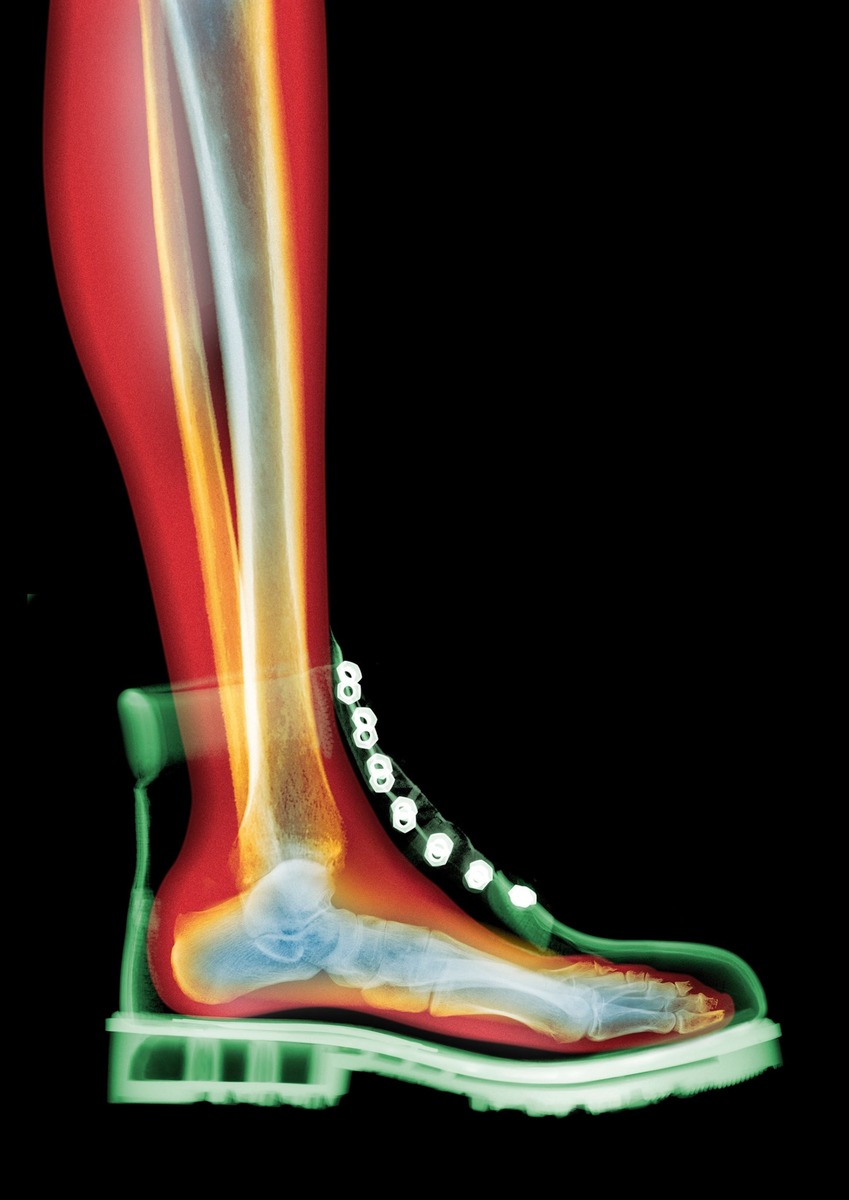

На цветном рентгеновском снимке в стиле МРТ видно, как шнуровка ботинка обхватывает стопу и распределяет давление вдоль свода стопы и лодыжки. Формируя движения стопы и распределение веса, такая обувь может влиять на осанку, походку и боль во всём теле.